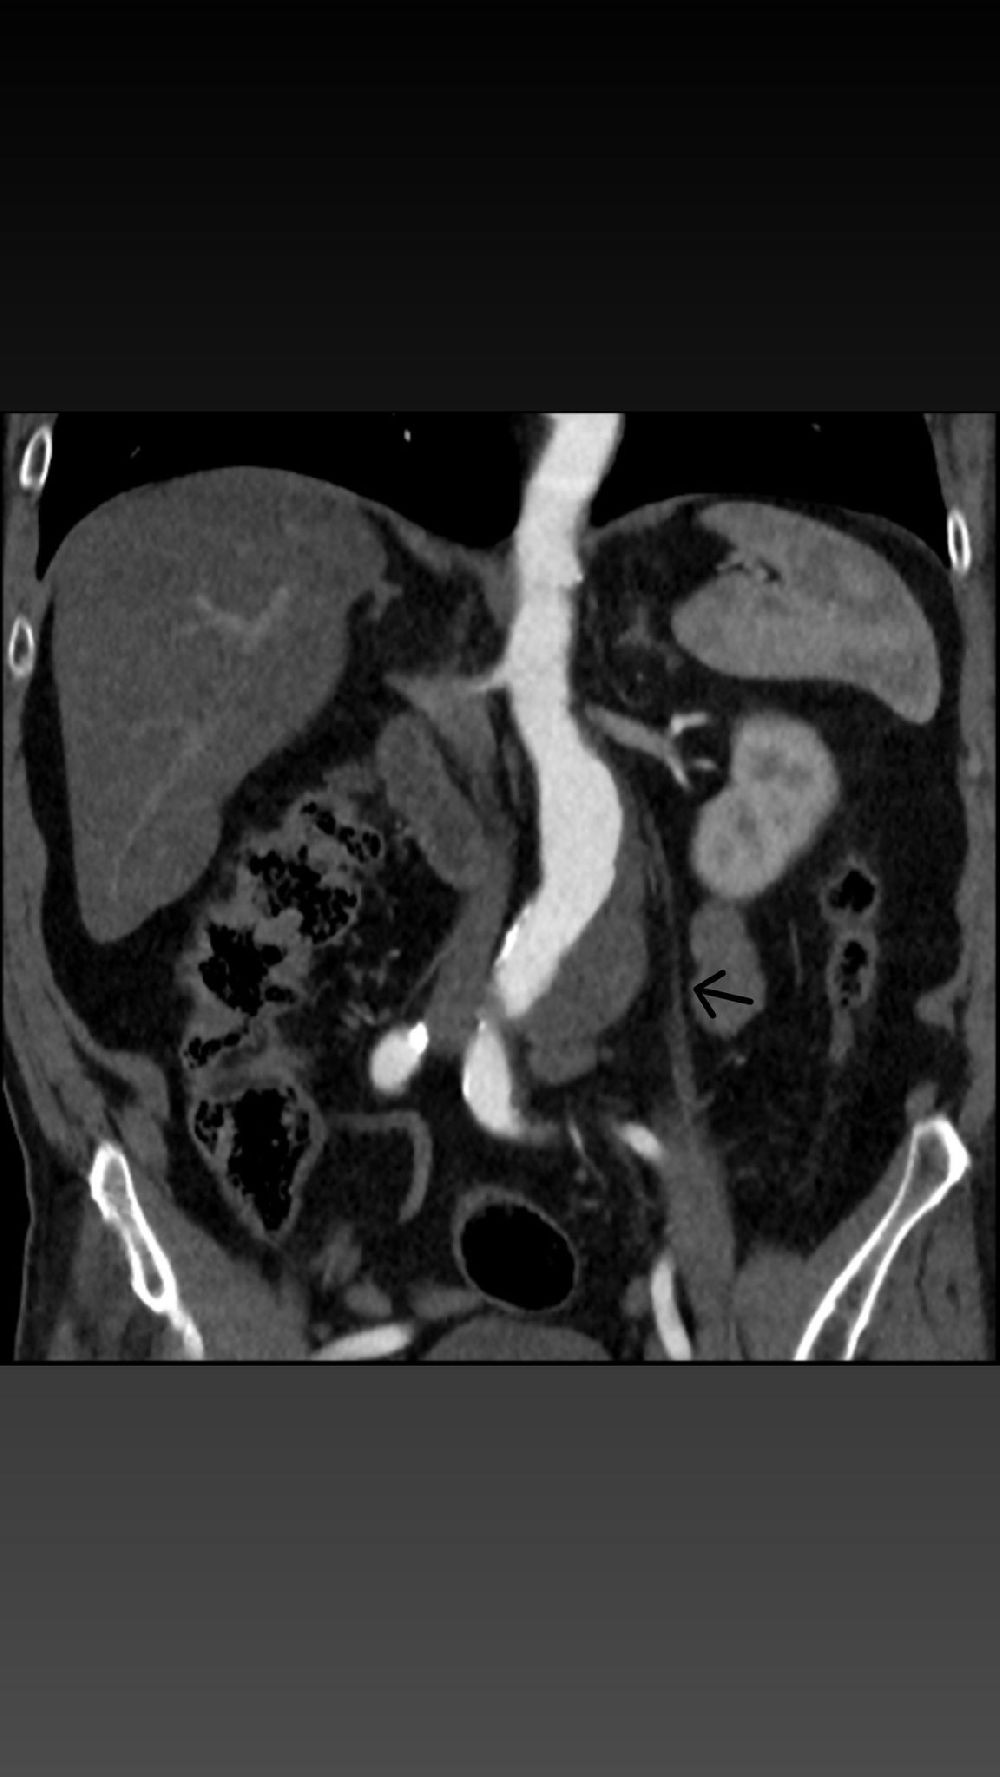

Karın aort anevrizması, vücudun en büyük atardamarı olan aortun karın bölgesindeki genişlemesiyle ortaya çıkan, ciddi ve hayati risk taşıyan bir hastalıktır. Kontrol altına alınmadığında damarın yırtılmasına (rüptür) neden olabilen bu durum, erken müdahale gerektiren kritik bir sağlık sorunudur. 68 yaşındaki hastanın yapılan tetkiklerinde, aort damarında 56 mm’ye ulaşan bir genişleme tespit edildi ve bu yüksek riskli tablo karşısında EVAR prosedürü uygulanmasına karar verildi.

Operasyon, kasık bölgesinden yapılan küçük kesiler aracılığıyla minimal invaziv şekilde gerçekleştirildi. Genişleyen damar bölgesine özel bir greft kaplı stent yerleştirilerek anevrizmanın bulunduğu bölge izole edildi ve damarın normal akışı sağlandı. Bu yöntem sayesinde hastanın iyileşme süresi de açık cerrahiye göre daha hızlı ve konforlu hale geldi.